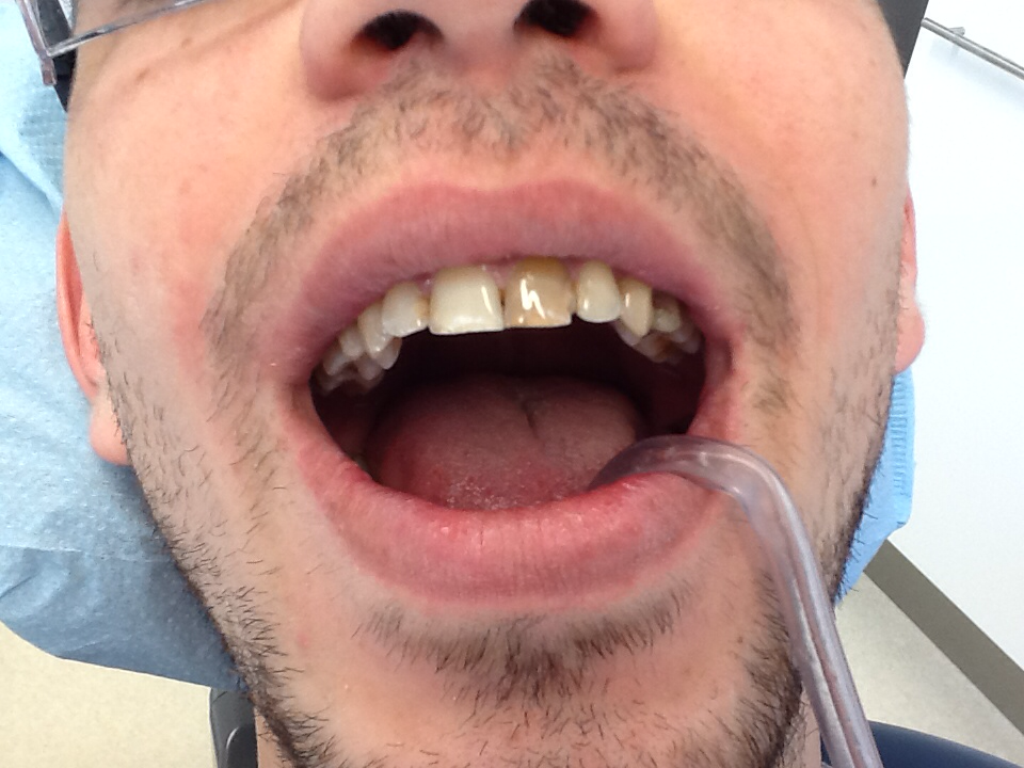

Before

After

Patient dissatisfied with his smile, cosmetic composite correction on one visit.